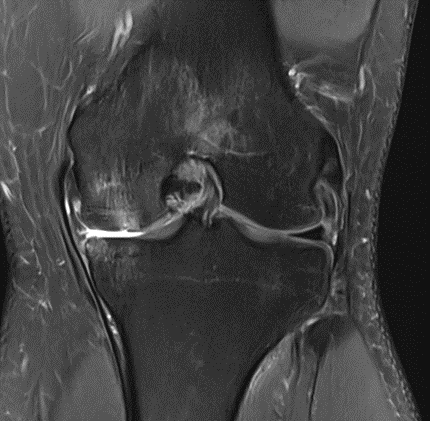

MRI scans illustrating the improvements regarding Group 2 are presented below, showing pre-treatment images with evident cartilage defects, pronounced bone marrow edema, and synovial inflammation, followed by post-treatment scans demonstrating improved joint structure, reduced edema, and decreased inflammation (Figures 12-29).

Figure 12: Female, 59 years, pre-intervention MRI.

Figure 13: Female of figure 12, 59 years, two-month follow-up MRI: MSC plus ChondroFiller® liquid.